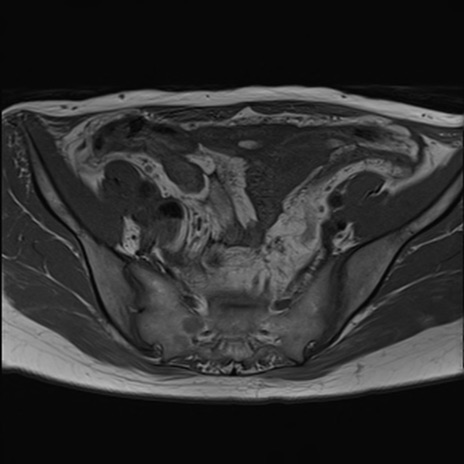

症例39 T1WI(横断像)

MRI(4日後)